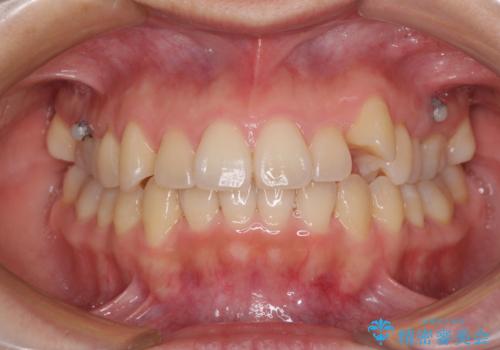

- 八重歯と前歯のデコボコを気にして来院された患者様です。

八重歯の他に、上顎歯列を狭窄しているという問題点がありました。

また、八重歯により上顎奥歯が前方に位置しており、咬み合わせの改善も必要な状況でした。